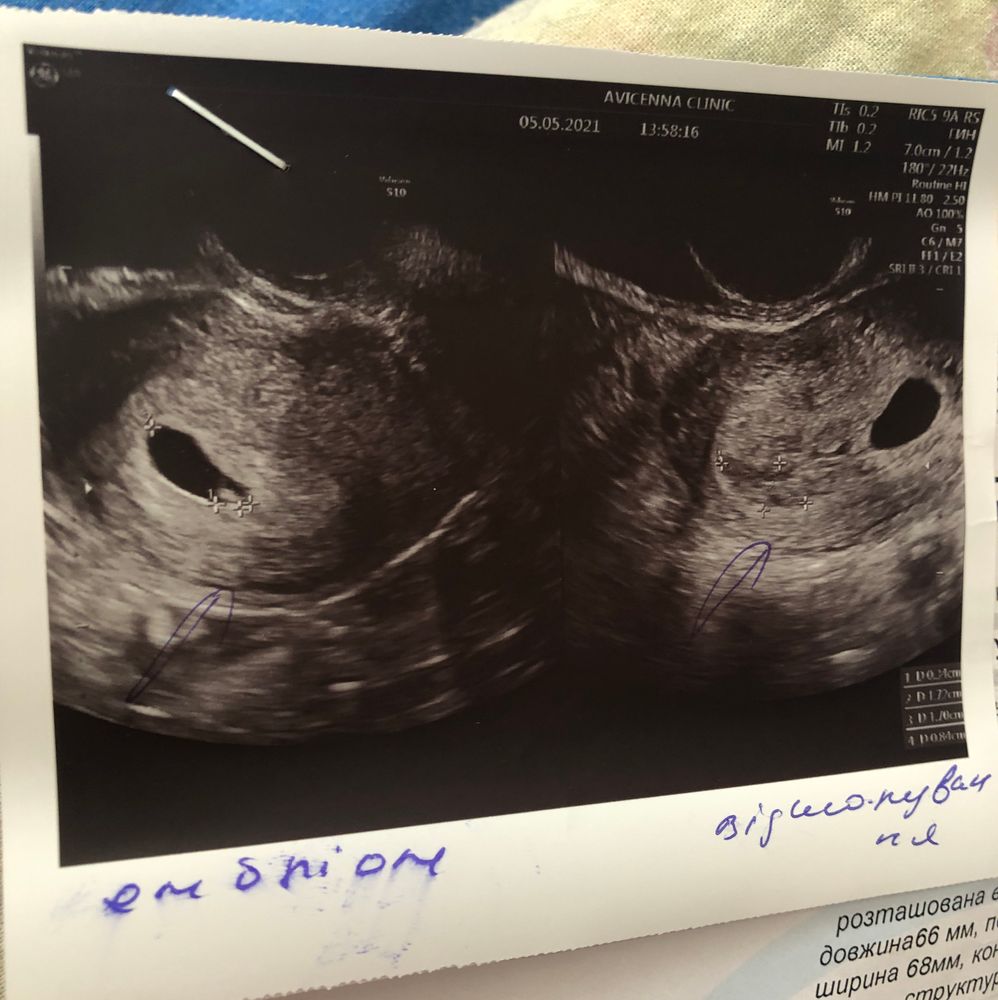

Первое узи🤍

У меня по месячным было 6+5 а по овуляции примерно 5+5 свд 13мм ктр 3мм сб +, все у вас хорошо

Ну маленькая отслойка, организуется и все. А так все отлично. Растите.